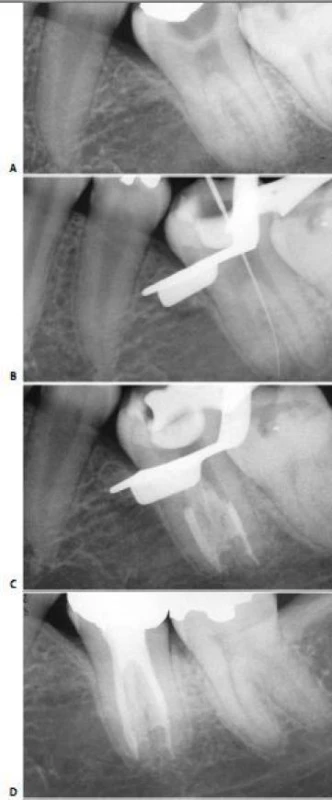

Ống xa thường có hướng khá thẳng, ngoại trừ hầu hết phần chóp thì thường nghiêng xa (hình 11.117). Lý do vì sao cong về phía xa cũng dễ hiểu, nếu như biết rằng hàm dưới vẫn còn phát triển về phía gần khi răng đã hoàn thành việc đóng chóp. Chóp chân răng hình thành xung quanh một cuống mạch máu, vào một thời điểm nào đó cũng sẽ nghiêng theo chiều gần xa.

Điều quan trọng là phải biết ống tủy có cong và dùng dụng cụ nhỏ, uốn cong trước. Một dụng cụ thẳng với kích thước không phù hợp sẽ bị cản trở bởi thành ngoài của chỗ cong, tạo cảm giác như dụng cụ đã đến tiếp xúc với chỗ thắt ở phía chóp hoặc chỗ nối cement ngà. Một dụng cụ nhỏ, uốn cong trước thì lại có thể dễ dàng vượt qua được đoạn cong ở phía chóp.

Hình 11.117. A. Phim trươc điều trị: ống tủy được điều trị bởi bột nhão iodoformic  B. Làm cong file 8: dễ dàng qua chỗ cong của ống tủy  C. Phim sau điều trị. D. Phim 2 năm sau. Chỗ cuối của vị trí trám bít ống tủy cách đỉnh chóp ít nhất 3mm.